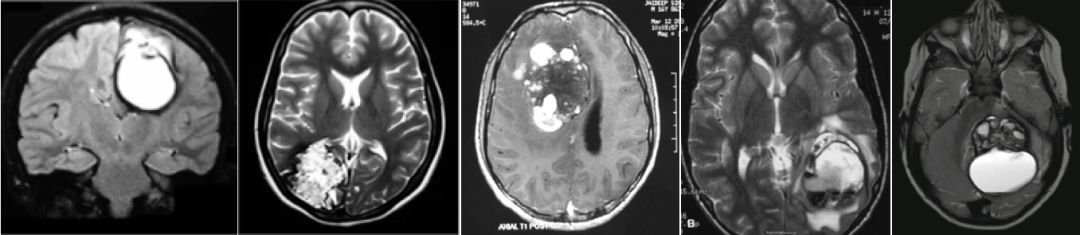

GCM的神经影像学诊断上具有挑战性,因为它们较为罕见。GCM的影像学表现可能从完全囊性病变到类似肿瘤的强化表现和占位效应(图7)。

图7. 不同类型GCM的影像学表现

病灶信号混杂不均,呈“桑葚”样,伴有囊变,边界清,增强后实质部分强化可有可无。肿瘤病变可能与GCMs的表现非常相似,尤其是出血性转移瘤、黑色素瘤和一些胶质瘤,如少突胶质细胞瘤和毛细胞型星形细胞瘤伴钙化或出血,有时可误诊为巨大畸胎瘤(8)。明显出血的GCM在MR上可表现为T1、T2上信号不一的“多囊性血泡”[9]。GCM在CT上一般呈现高密度影,可伴有瘤周水肿,可见“爆米花”样结节状钙化。